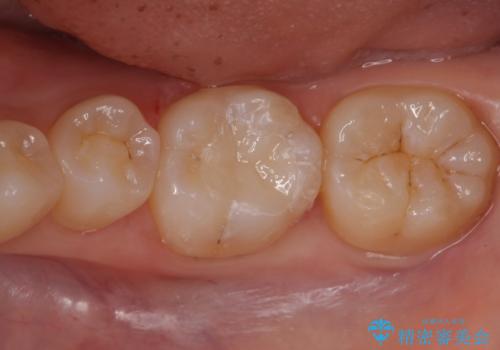

そのため②のe-maxインレーでの治療の方針になった。

- e-maxインレー 7.7万円 費用は治療当時の料金となります

多少大きく削ることになってしまったが、希望に沿った処置となり、

満足して頂けました。